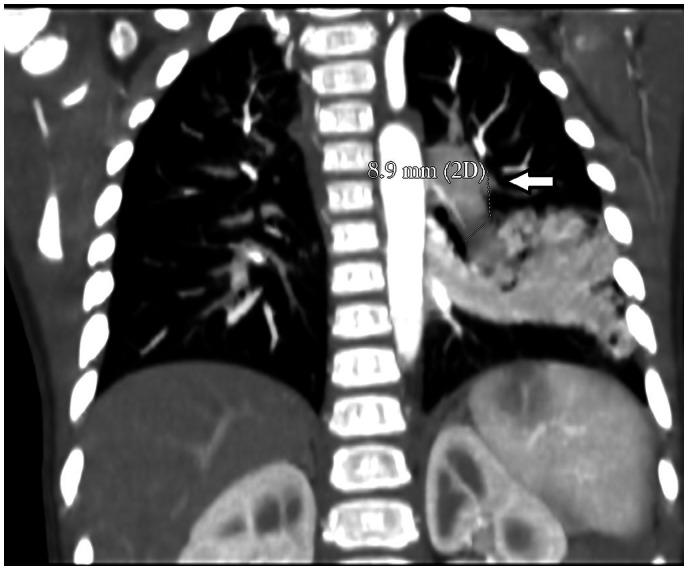

Eighteen months old female child was referred to our centre due to unexplained central and peripheral cyanosis. Based on the agitated saline contrast echocardiography study, computed tomography scan confirmed the presence of abnormal vasculature at the left lower lobe. Percutaneous closure of the PAVM was performed using Amplatzer Duct Occluder type 1 device. The genetic study revealed a pathogenic mutation in the endoglin gene, which is a known cause of hereditary haemorrhagic telangiectasia (HHT) inhered in an autosomal dominance pattern.

一名18个月大的女童因不明原因的中枢性和外周性发绀被转诊至我院。基于生理盐水对比剂超声心动图检查,计算机断层扫描证实左下叶存在异常血管。使用1型Amplatzer导管封堵器对PAVM进行了经皮封堵。基因研究显示内皮素基因存在致病性突变,这是常染色体显性遗传的遗传性出血性毛细血管扩张症(HHT)的已知病因。